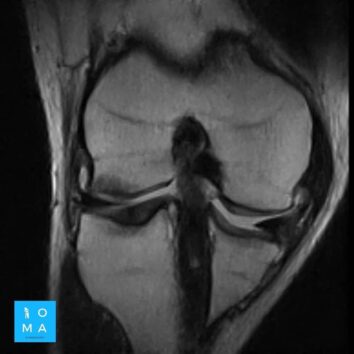

En la evaluación con medio de contraste, se evalúa la relación arterial y de las venas, esto puede servir para buscar la arteria central relacionada con la hiperplasia nodular focal o bien, para evaluar la relación con las estructuras vasculares que son muy importantes para el planeamiento quirúrgico .

en este caso, aún cuando los hallazgos son atípicos tanto para hiperplasia nodular focal como para adenoma, nos inclinamos hacia el diagnóstico de adenoma debido a los antecedentes de la paciente, el tamaño de la lesión, el área de sangrado, el contenido de grasa.